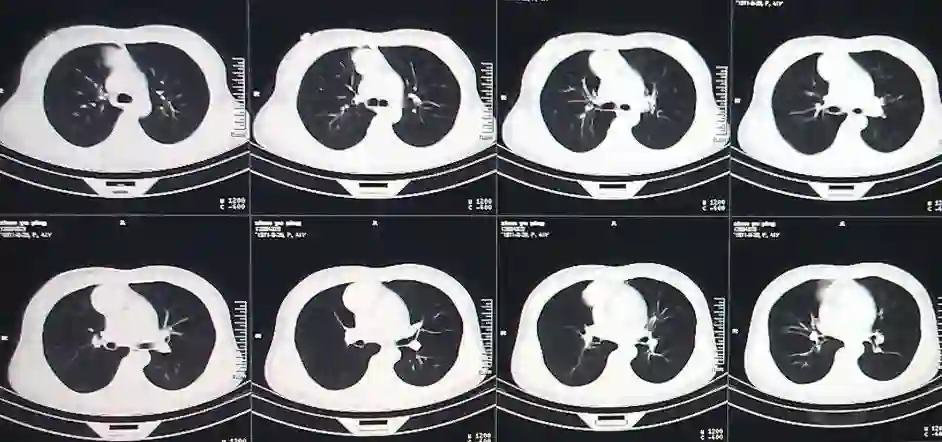

肺结节AI辅助诊断

肺癌,在我国的发病率、死亡率极高,伤害着无数家庭。在我国每年都有近60万人死于肺癌。肺癌防治的重要手段是早期筛查,其中胸部低剂量CT是国际公认的有效手段。而在如今传统的阅片模式中,医学影像面临医疗从业人员短缺,人工分析模式精准度受限,以及基层医院医疗机构诊断水平参差不齐,高年资医生匮乏,易出现漏诊、误诊等问题。

现阶段市场中的人工智能肺CT产品已经实现了肺结节的检出功能,可支持包括:实性结节、磨玻璃结节、形态不规则的大结节、血管旁结节、肺门区结节等。支持提供量化信息检测如自动测量病灶的长径、短径、CT值、体积等参数。支持提供定性信息检测如病灶密度:实性、部分实性、磨玻璃、钙化,以及病灶良恶性等级分类:良性、疑似良性、恶性、疑似恶性。另外支持多种伴随征象的检出,如边界模糊、分叶、毛刺、胸膜牵拉、血管集束等。此外还有肿块、斑片、网影、条索影、气胸、胸腔积液等病变检出。部分产品还含有胸部骨质病变筛查功能,自动检出骨折,支持3D的可视化帮助医生定位,进行全面智能分析与诊断。

在国内,各企业积极响应国家基础医疗建设和分级诊疗制度实施的号召,应用深度学习的技术,携手各大高校科研机构与国内医院,运用国际前沿技术,使人工智能医学影像诊断达到国际领先水平,在各系统疾病的精确诊断方面处于行业领先,为医生进一步诊疗决策提供临床建议。

很多创业公司都研发了肺部CT检测相关产品,此类产品也是国内医学影像创业公司的门槛产品。该方向起源于国际LIDC以及LUNA的肺结节检出竞赛。目前,各个公司推出了他们的相关产品。例如,深睿医疗(DeepWise)推出的Dr.WISE CAD医疗影像诊断系统;推想科技(Infervision)的InferReadCTLung产品系统;依图医疗(YITU)、图玛深维(12Sigma)、医准智能(MEDICAL AI)等公司的产品,均已经在市场上投入使用。上市公司方面,阿里健康研发的医疗AI产品“Doctor You”已经公开发布,此外还有科大讯飞、中国平安集团旗下平安科技、腾讯觅影等。

在国外,具有代表性的有谷歌的深度思维(DeepMind,美国)、西门子(SIEMENS,德国)、飞利浦(PHILIPS,荷兰)、ARTERYS、通用电气(GE,美国)等公司研发的相关产品,均可以支持病灶筛查、定位、定量标注、诊断等一系列阅片流程,从而推进精准医疗建设,优化病患就医体验。